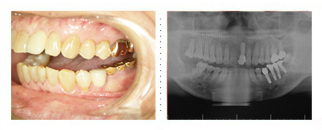

82歳 男性 当医院でのインプラント第一号の方です。

左下に3本インプラント治療をし、約20年が経ちました。